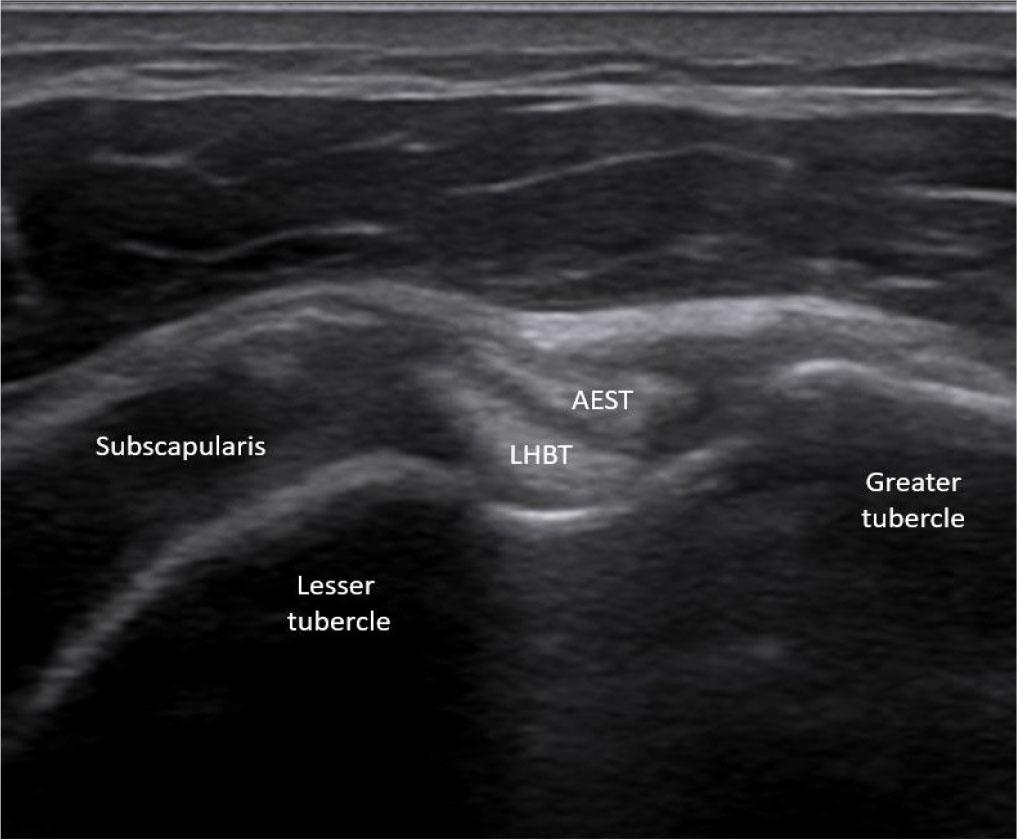

Ultrasound image showing normal aponeurotic expansion of supraspinatus tendon (AEST) anterolateral to the long head of the biceps tendon (LHBT) at the intertubercular groove

At the level of the rotator interval, AEST was assessed for echogenicity, intrasubstance tears, and its relationship to the LHBT and subscapularis tendon (Fig. 3), while the supraspinatus was checked for tear-related changes. AEST was then examined at the intertubercular groove to determine its position (intragroove, subluxation, dislocation, medial dislocation; Fig. 4), along with LHBT and subscapularis integrity. The remaining shoulder structures, including the other rotator cuff tendons and the glenohumeral and acromioclavicular joints, were systematically reviewed. The findings are summarized in Tab. 1.